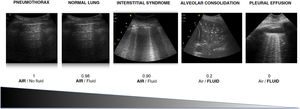

Air/fluid ratioThe different ultrasound patterns reflect a different air/fluid ratio (Fig. 3).5

Ultrasound patternsPattern A: characterized by the presence of “sliding” (Video 1), and the artifacts defining it are the A-lines (Fig. 4).5,7 On exploring in M mode, we observe the “seashore sign” (Suppl. Fig. 2).5

Pattern A’: characterized by the absence of “sliding” and the presence of A-lines (Video 2). This pattern suggests the existence of pneumothorax. The latter is confirmed by the identification of the “lung point”, which is the point where the two pleural layers again slide over each other in the context of non-massive pneumothorax (Video 3).6

Pattern B: occupation of the pulmonary interstice by fluid, inflammatory products or fibrotic material gives rise to two regions with different acoustic impedance characteristics, exhibiting the artifacts typical of this pattern, the B lines (Video 4).6 In order to confirm a B pattern, we need to evidence three or more B lines between two ribs, in two or more regions, and separated by ≤ 7 mm.

Pattern B’: this is similar to the B pattern, with the absence of “sliding”. It is visualized in disorders such as acute respiratory distress syndrome (ARDS), pneumonias and lung fibrosis, where pleural adherences are produced that result in a decrease or absence of “sliding”, along with pleural thickening or the appearance of pleural anomalies (Video 5). Lung involvement is characteristically heterogeneous, with the appearance of different ultrasound patterns in the same patient.8

Pattern C: this is characterized by the “tissue-like sign” or “shred sign”. In the “tissue-like sign”, the echogenicity of the consolidated lung parenchyma is similar to that of the liver. Within the consolidated component we can visualize hyperechogenic images corresponding to the air bronchogram (Fig. 5). The “shred sign” in turn consists of consolidations of smaller size manifesting as a disruption of the pleural line, with an irregular or serrated margin that separates the consolidated component from the aerated lung (Fig. 6) (Video 6).5